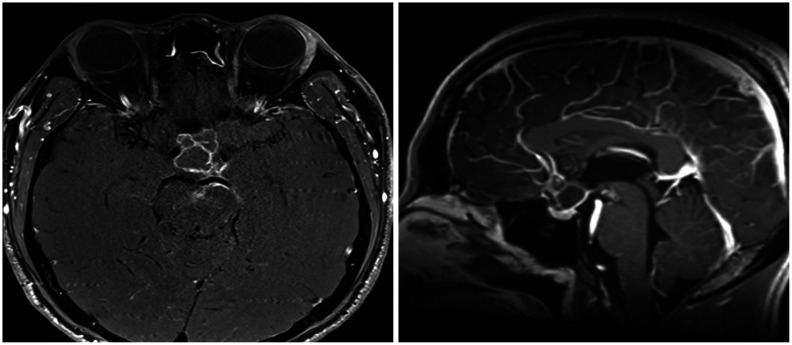

Recurrence of Rathke's cleft cysts (RCC) following surgery is not uncommon. We present a 33-year-old male patient with chronic headache and visual disturbances whose MRI showed mostly cystic, suprasellar mass with peripheral enhancement. Endoscopic extended transsphenoidal approach and tumor resection was performed and RCC was pathologically confirmed postoperatively. Early recurrence was first suspected at 3 months following surgery, and his serial MRIs showed a recurred mass without associated clinical symptoms. Upon further histopathological study, extensive squamous metaplasia and high Ki-67 were seen. Also, in this study, we discuss important factors associated with cyst recurrence following surgery.